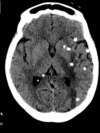

Variante Creutzfeldt

Doença de Creutzfeldt Jacob

Qual o padrão da imagem na DCJ?

Hiperintensidade T2 e especialmente na difusão em regiões de núcleos da base, tálamos e córtex. O hipersinal no pulvinar do tálamo e no núcleo dorsomedial é descrito como sinal do taco de hockey. Lobos mais frequentemente envolvidos são frontal e parietal.

Qual o padrão da doença de creutzfeldt jacob?

Lesões que podem ser bilaterais e simétricas, com hipersinal em T2 nos nucleos da base: estriado bilateral, tálamo (sinal do pulvinar e do taco de hóckey), córtex e substância branca; A restrição à difusão é o sinal mais sensível;